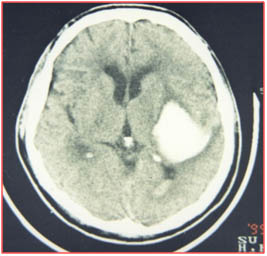

腦出血術(shù)前

術(shù)后第1天